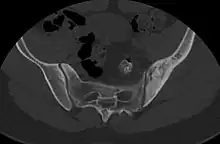

- ↑ Nguyen, Nghi; Khan, Mujahid; Shah, Muhammad (2017). "Primary B-cell lymphoma of the pelvic bone in a young patient: Imaging features of a rare case". Cancer Research Frontiers. 3 (1): 51–55. doi:10.17980/2017.51. ISSN 2328-5249.